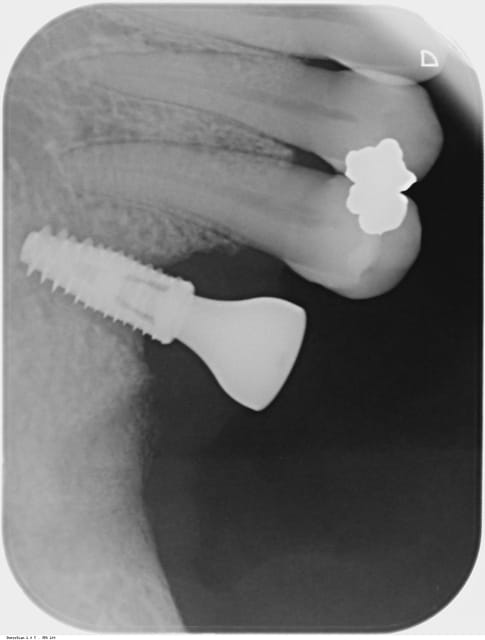

C'est un implant distal, aucune protection en postérieur, perso je pense qu on ne prend pas assez en considération la puissance de la langue et des joues.

ta bague de cicatrisation est haute et large ce qui permet de forces latérales considérables, et tu dis toi même que tu "n’étais" peut-être pas satisfait de ta stabilisation primaire!

Je partage cet avis au sujet de la vis de cicatrisation, je la trouve trop haute (grand effet de levier ) et trop large ( grand plateau occlusal avec lequel le patient mastique) .

On devine aussi l'alvéole de la 7 sur la radio : l'extraction n'est-elle pas trop récente ?

Tout à fait d'accord avec les avis précédent : la vis de cicatrisation (qui semble être une 6,5 *5 la plus grosse de la gamme) donne en effet trop de prise à la langue en cette position . ce qui semble être confirmé par le fait que le patient ai senti l'implant bouger .

un deux temps chirurgical est bien plus sur dans ces zones surtout en cas de stabilité primaire faible

mais dans la littérature, 35 Ncm, c'est une valeur acceptable pour envisager une MCI...donc moi non plus je ne crois pas trop à cette histoire de vis de cicat, d'autant qu'à la radio j'ai pas l'impression qu'elle dépasse tant que çà de la muqueuse gingivale...